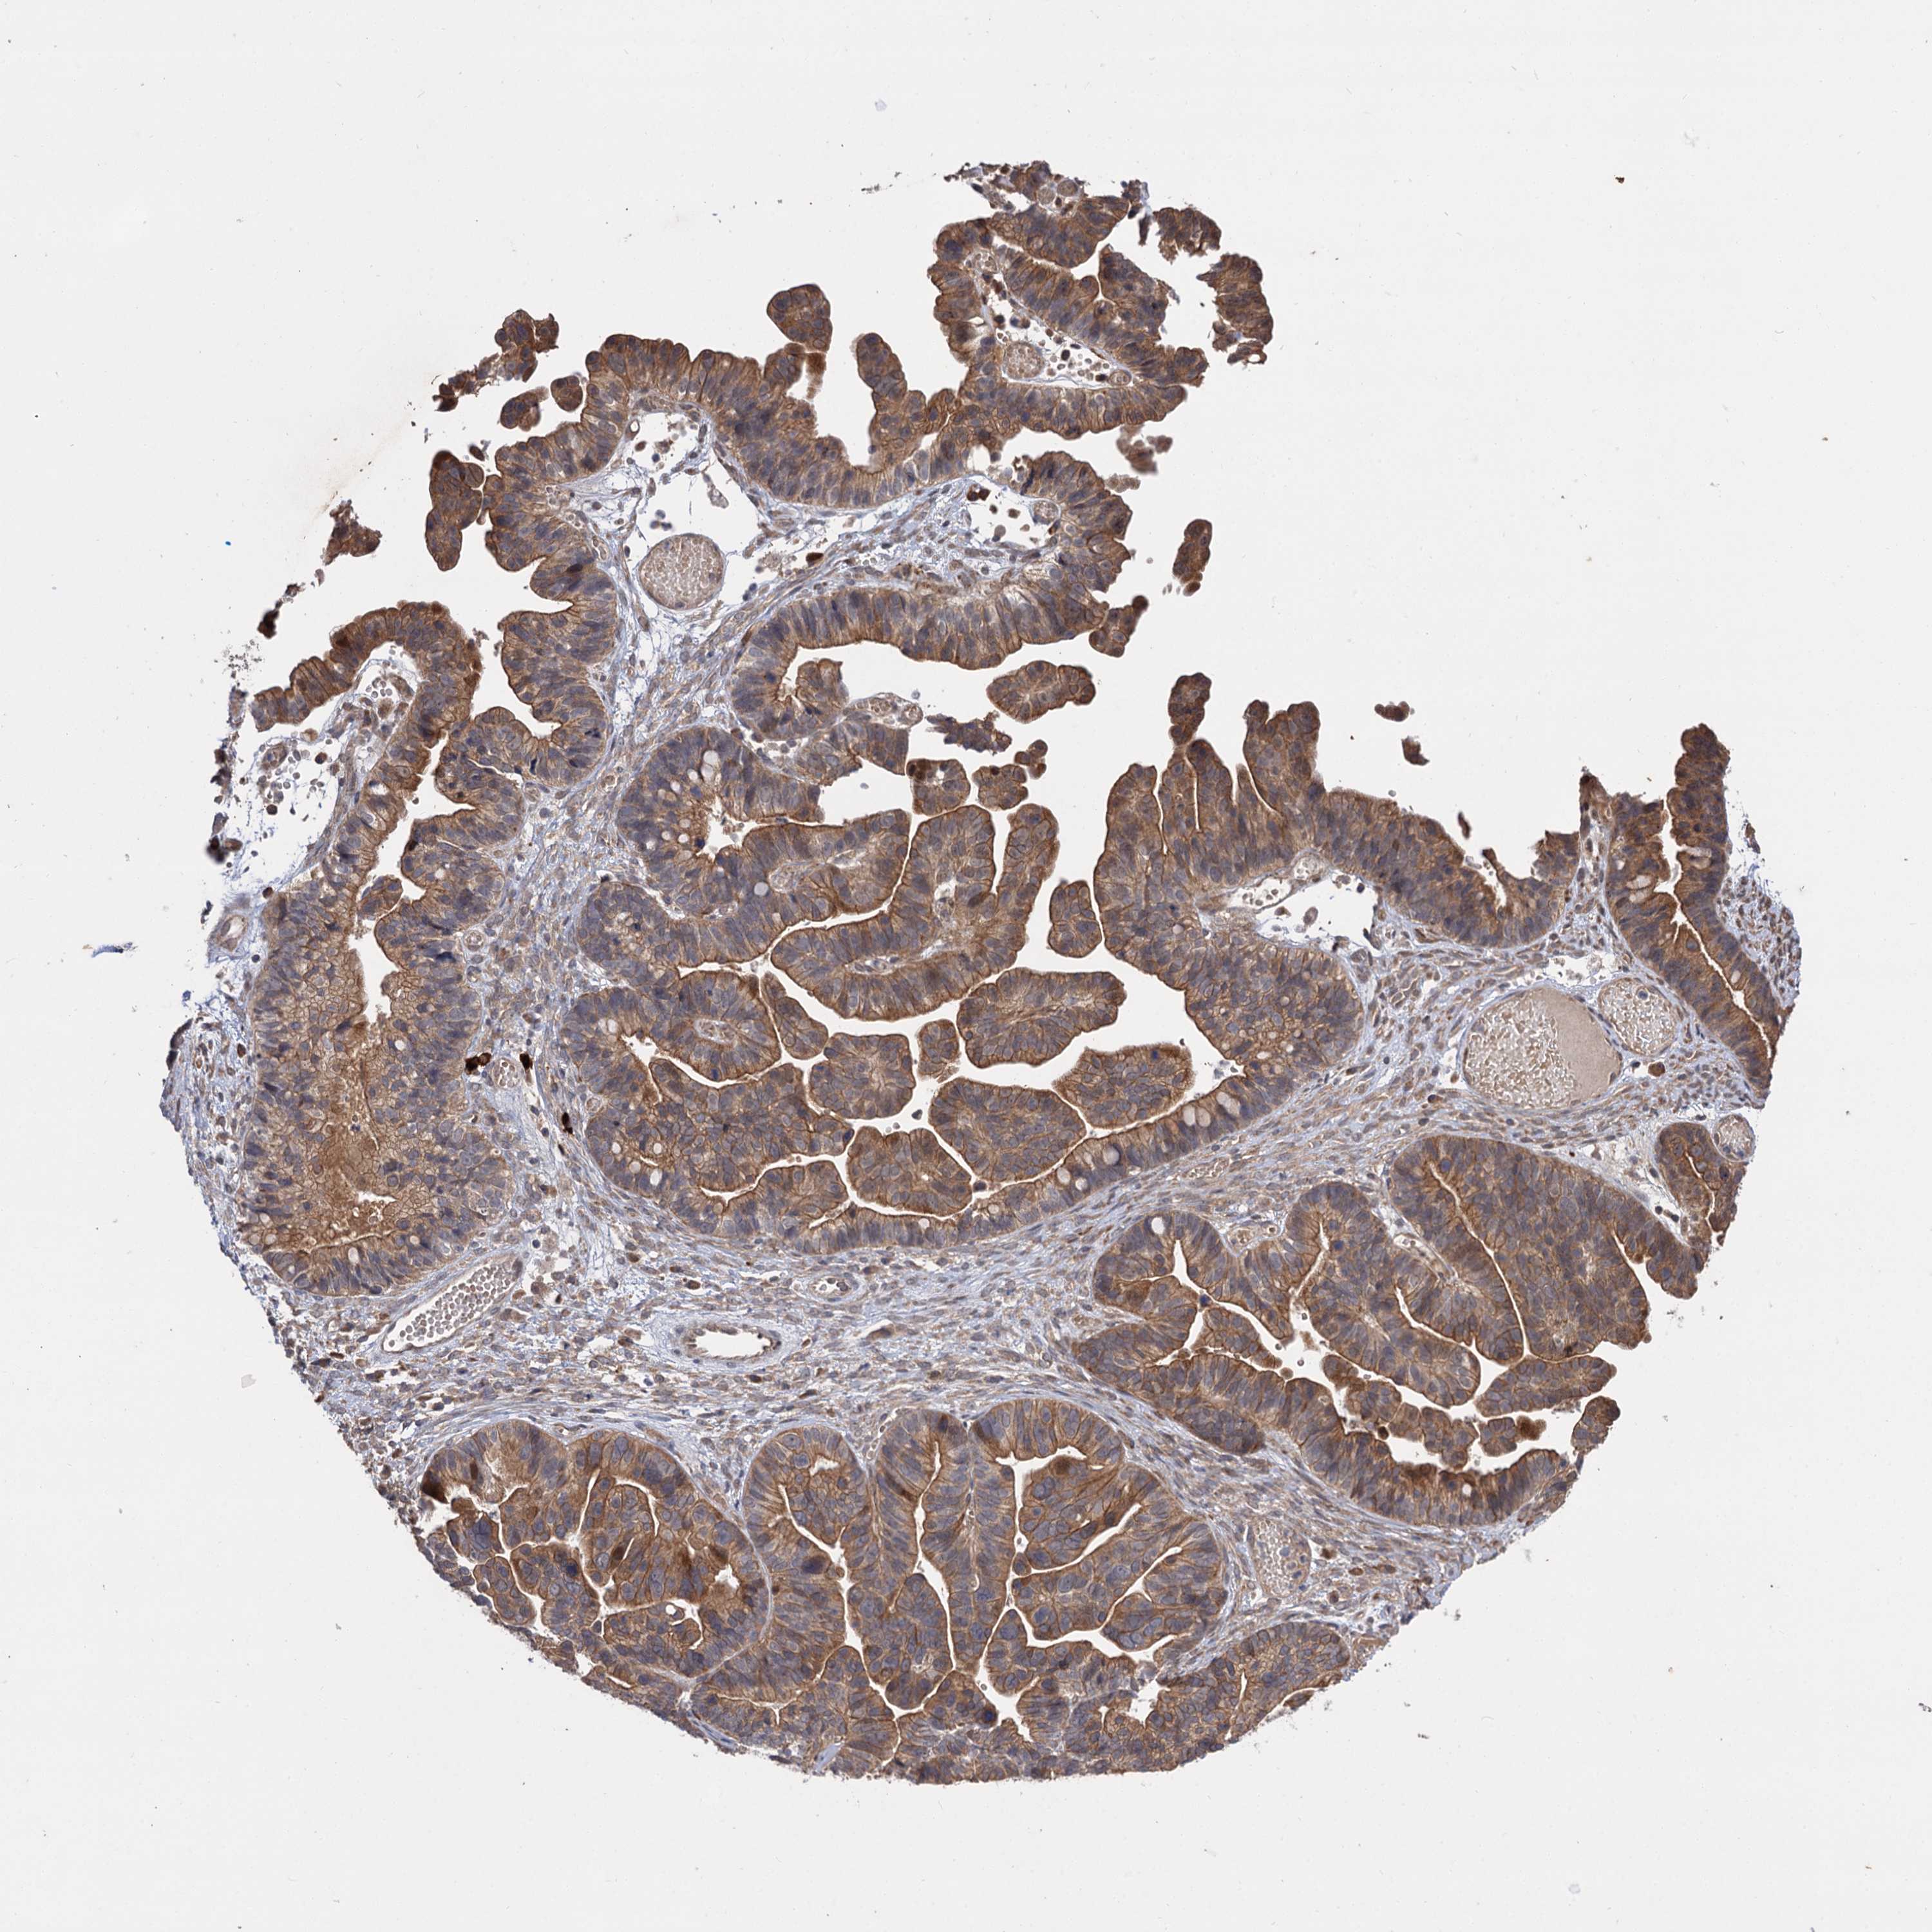

OVARIAN CANCER - Protein expressioni

A mouse-over function shows sample information and annotation data. Click on an image to view it in a full screen mode. Samples can be filtered based on level of antibody staining by selecting one or several of the following categories: high, medium, low and not detected. The assay and annotation is described here.

Note that samples used for immunohistochemistry by the Human Protein Atlas do not correspond to samples in the TCGA dataset.

Antibody stainingi

Antibody staining in the annotated cell types in the current human tissue is reported as not detected, low, medium, or high, based on conventional immunohistochemistry profiling in selected tissues. This score is based on the combination of the staining intensity and fraction of stained cells.

Each image is clickable and will lead to virtual microscopy that enables deeper exploration of all samples and also displays staining intensity scores, fraction scores and subcellular localization as well as patient and tissue information for each sample.

Antibody HPA038850

Antibody HPA038851

Cystadenocarcinoma, serous, NOS

Carcinoma, endometroid

Cystadenocarcinoma, mucinous, NOS

Carcinoma, NOS